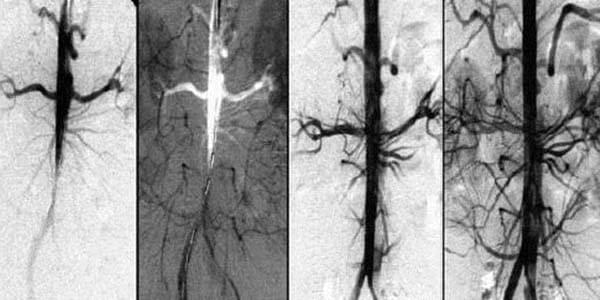

• Zerebrovaskuläre Erkrankungen. Es handelt sich um eine Unterbrechung der Blutgefäße im Gehirn, die zu einer mangelnden Versorgung der Gehirnzellen und damit zu einer Schädigung der Gehirnsubstanz führt. Dies führt häufig zu einem Schlaganfall, der zum Tod oder zu Behinderungen führt.

Wie jedes andere System muss auch das menschliche Kreislaufsystem regelmäßig gewartet und repariert werden. Wenn zum Beispiel Wasserleitungen im Laufe der Zeit verstopft und von innen verkalkt sind, steigt das Risiko eines Rohrbruchs - denn sie müssen die gleiche Wassermenge wie früher durch eine engere Öffnung leiten, was zu einem höheren Druck führt.

Wenn die Blutgefäße des Herzens (Koronararterien) durch Cholesterinablagerungen verstopft sind, verursacht dies zunächst Angina pectoris, kann dann aber zu einem Herzinfarkt führen. Und Blutgefäße, die an Kapazität verloren haben und das Gehirn nicht mehr richtig mit Blut versorgen, sind ein sicherer Weg zum Schlaganfall.

Die Blutzirkulation wird systemisch wieder hergestellt - in allen Gefäßen, Arterien und Kapillaren.